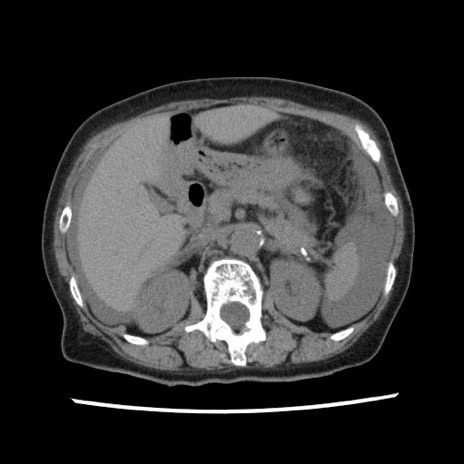

【症例】80歳代女性

【主訴】腹痛

【現病歴】8時間前から腹痛あり来院。

【既往歴】糖尿病、脂質異常症、子宮体癌にて子宮全摘術

【身体所見】意識清明・会話良好だが腹痛で苦悶様、全腹部にわたって反跳痛と圧痛あり

【データ】WBC 13600、CRP 0.14、LDH 224、CK 90